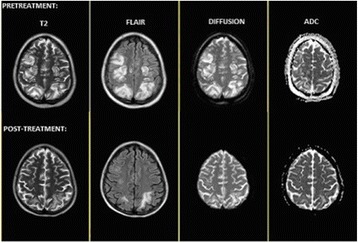

P206 A life threatening emergency: PRES - cases series and literature review

S Silva Passos, F Maeda, L Silva Souza, A Amato Filho, T Araújo Guerra Granjeia, M Schweller, D Franci, M De Carvalho Filho, T Martins Santos, P De Azevedo

University of Campinas, Campinas, Brazil

Introduction: To describe comorbidities, clinical presentation, diagnostic method, treatment and outcome of 6 patients with Posterior Reversible Encephalopathy Syndrome (PRES). PRES is consequence of a reversible subcortical brain edema in patients with acute neurological symptoms, such as headache, impaired sensorium, visual abnormalities, nausea/vomiting, cerebellar syndrome, focal neurological deficits and seizures. Causes include hypertension, eclampsia/pre-eclampsia, sepsis, autoimmune disease, immunosuppressive agents, chemotherapy and renal failure. Radiological findings on computed tomography (CT) and magnetic resonance imaging (MRI) include abnormalities of white and grey matter, predominantly affecting parietal and occipital lobes. The treatment is based on the removal of the underlying cause.